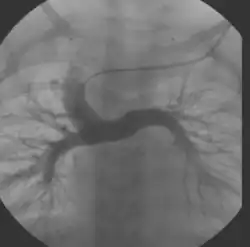

Obecnie operacja Fontana jest najczęściej dwuetapową operacją, stosowaną jako drugi i trzeci etap procedury Norwooda. Zabieg polega w pierwszym etapie na wykonaniu dwukierunkowego zespolenia Glenna, lub tzw. operacji hemi-Fontana. Krew z żyły głównej górnej (VCS) spływa bezpośrednio do tętnic płucnych, a z żyły głównej dolnej (VCI) miesza się nadal z krwią tętniczą na poziomie serca. W drugim etapie operacji Fontana wykonuje się najczęściej zewnątrzsercowe połączenie VCI z tętnicą płucną lub połączenie wewnątrzsercowe (tzw. operacja de Levala – Total Intracardiac Cavo−Pulmonary Connection). Od tego momentu krążenie duże (systemowe) i małe (płucne) są oddzielone, gdzie krew żylna przepływa przez płuca pod wpływem ciśnienia żylnego, a krew tętnicza pompowana jest do aorty przez pojedynczą komorę serca[2]. Najczęściej stosuje się dwie modyfikacje operacji Fontana:

- zewnątrzsercową (obecnie preferowaną), gdzie żyłę dolną główną łączy się z prawą gałęzią płucną przy użyciu protezy wykonanej z Gore-Texu[2][12][13]. Po wprowadzeniu przez Marcellettiego w 1990 zewnątrzsercowego zespolenia VCI z tętnicą płucną metoda ta jest aktualnie metodą z wyboru (polecana jako najlepsza) i jest przeprowadzana najczęściej w krążeniu pozaustrojowym na bijącym sercu, ale może być też wykonana przy przeciwwskazaniach, bez użycia krążenia pozaustrojowego stosując na czas zespolenia omijające połączenie między VCI i prawym przedsionkiem serca[2][14].